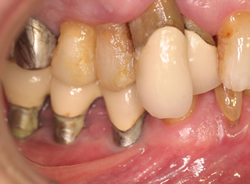

先日来院した患者さんはインプラントのまわりに角化歯肉がない状態のためプラークコントロールができずインプラント周囲炎をおこしていました。歯肉が痩せて薄くなってますす。